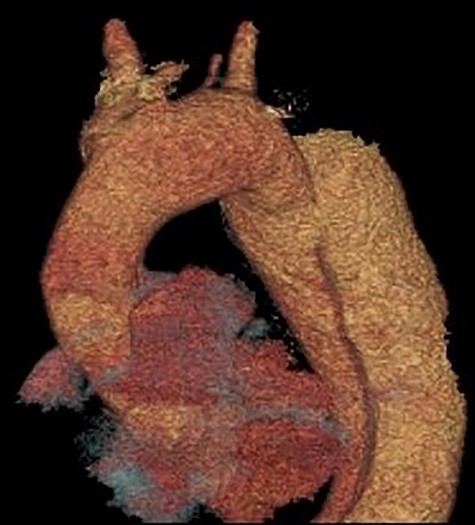

Coronal section CT scan images demonstrating the newly arranged epiaortic reconfiguration on left (A) and on the right (B) the deployed FET and antegrade flow in the descending thoracic aorta through the true lumen.

Cardiopulmonary bypass support was established using right atrial drainage and right axillary artery return. During cooling to 18°C, the aorta and epiaortic arch vessels were mobilized and encircled with tapes. At 21°C, the heart was fibrillated, aortic cross-clamp applied and antegrade cold blood intermittent cardioplegia administered to arrest the heart. At 18°C, neuroprotective protocol (topical ice to the head, intravenous steroids and mannitol administration with near infrared spectroscopy monitoring of cerebral saturations) was instituted and circulatory arrest commenced. The ascending aorta was transected 1 cm proximal to innominate artery and aortic arch inspected. Selective antegade cerebral perfusion was commenced. The aortic arch was divided in Zone 2 in order to protect the recurrent laryngeal nerve. The origin of the aberrant left vertebral artery and left subclavian artery were oversewn with a running 4/0 prolene suture. A 30/32/150 mm Thoraflex stent graft was deployed into the true lumen of the descending aorta. The cuff on the stent graft was anastomosed to the distal arch. Attention was then directed to the left common carotid and innominate arteries that were fashioned and anastomosed to the corresponding grafts on the stent graft. The aortic cross clamp was applied on the ascending aorta portion of the stent graft and total body circulation and rewarming was reinstituted. The ascending aorta was anastomosed to the stent graft 1 cm proximal to the innominate artery. A thorough de-airing drill was undertaken, the aortic cross clamp released and heart perfused. The graft on stent graft corresponding to the left subclavian artery was anastomosed and the origin on the aortic arch was oversewn. A 6-mm Dacron graft was then anastomosed to the transected left vertebral artery and origin on the aortic arch oversewn. The 6-mm Dacron graft was then anastomosed to the 8-mm side arm on stent graft corresponding to the perfusion arm. When fully rewarmed, cardiopulmonary bypass support was successfully weaned off and patient was in sinus rhythm requiring no inotropic support. Postoperatively, the patient made an uneventful recovery and was subsequently discharged home without complications and seen in the outpatient clinic as part of their routine surveillance. Computed tomography (CT) imaging performed as an outpatient demonstrated normal graft appearances, aortic arch and epiaortic vessel configurations (Fig. 3).